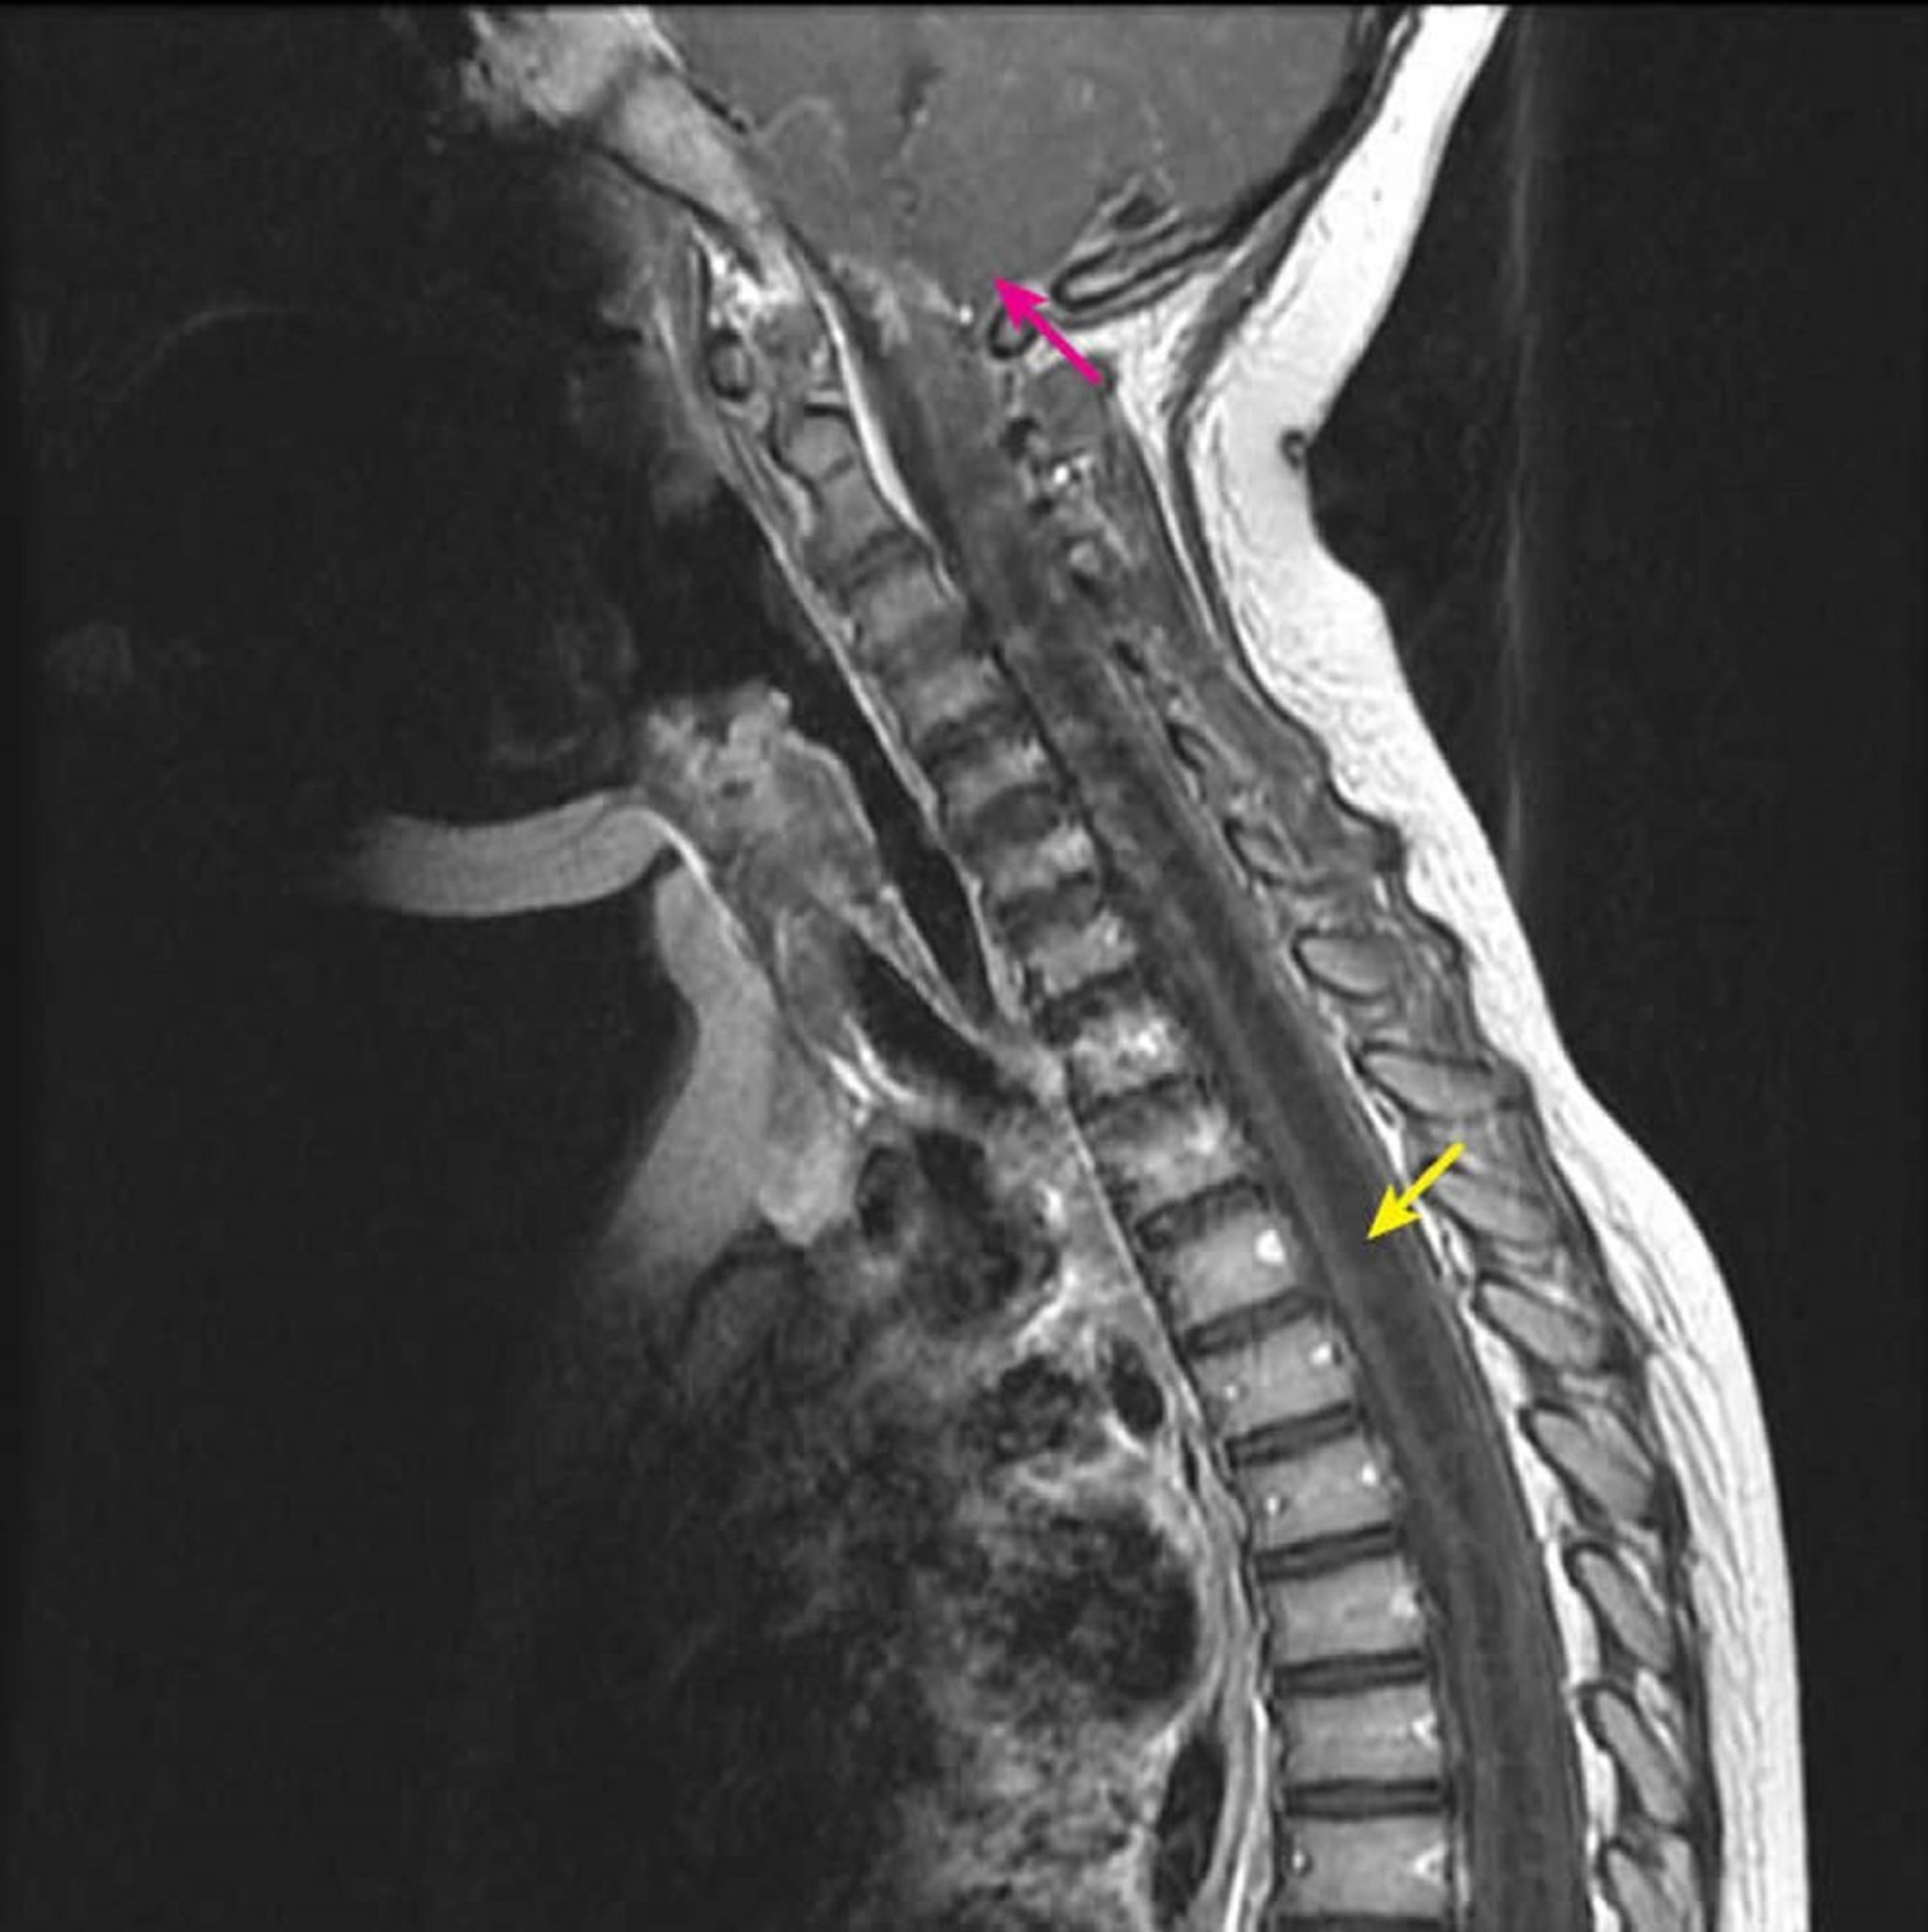

Siringomielia cervicotorácica

RM sagital pós-contraste ponderada em T1 mostra uma grande cavidade intramedular da medula espinal hipointensa em T1 característica de siringe (seta amarela). Estende-se do nível cervical C2-C3 inferiormente em uma criança com diagnóstico de malformação de Chiari I (seta rosa). Esse achado é definido como siringoidromielia, porque a siringomielia (cavidade excêntrica na medula espinal) não pode ser diferenciada da hidromielia (uma cavidade central na medula espinal) por testes de imagem.

Courtesy of John Tsiouris, MD, Division of Neuroradiology, New York–Presbyterian Hospital/Weill Cornell Medical Center.